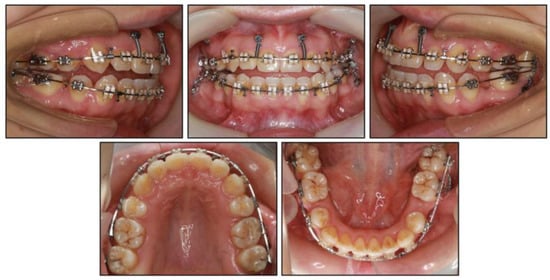

2.5. Treatment Results